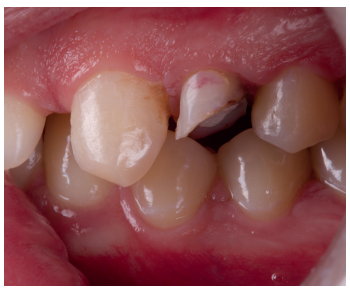

Se presenta en el Máster en Cirugía Oral, Implantología y Periodoncia de la Universidad Alfonso X El Sabio (Madrid, España) un paciente de 24 años derivado para exodoncia del primer premolar superior izquierdo y colocación inmediata de implante debido a una fractura corono-radicular como consecuencia de caries asintomática, con margen distal 2 mm subgingival y limitada estructura remanente (Figuras 1 y 2). Después de un estudio completo del caso, en colaboración con el Máster en Endodoncia de la misma facultad, se planificó la realización de la extrusión quirúrgica, endodoncia y posterior rehabilitación del diente. Dentro de este estudio resultaron de vital importancia las pruebas radiológicas, compuestas por radiografías periapicales y CBCT, que confirmaron la compatibilidad de la anatomía radicular con la realización de una extrusión mínimamente traumática.

con fractura corono-radicular.

fractura corono-radicular.